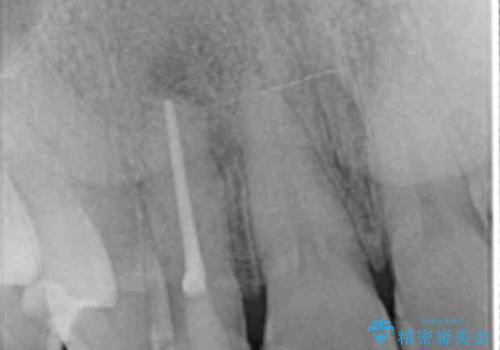

- 前歯の付近、歯ぐきを押すと違和感を感じその改善を求めて来院されました。

X線検査の結果、失活(感染根管)であることが判明したので、感染根管治療後セラミック補綴を計画します。